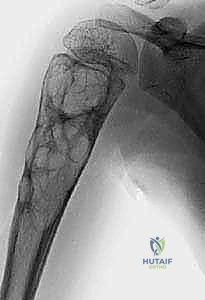

تُظهر هذه الأشعة السينية كيس عظم متمدد (ABC). لاحظ التوسع الكبير في العظم وترقق القشرة العظمية مقارنة بالكيس أحادي الغرفة.

في الـ ABC، تظهر الآفة غير مركزية، متمددة، وتدفع قشرة العظم للخارج لتصبح رقيقة جداً مثل "قشرة البيضة".

على النقيض تماماً من الـ UBC، يُعد كيس العظم المتمدد آفة حميدة ولكنها نشطة جداً وأحياناً عدوانية موضعياً. سمي بـ "المتمدد" لأنه يسبب انتفاخاً وتوسعاً ملحوظاً في العظم المصاب، وكأنه بالون ينتفخ داخل العظم.

- ألم متزايد: على عكس الـ UBC، يسبب الـ ABC ألماً مستمراً يزداد سوءاً مع مرور الوقت، وقد يوقظ المريض من النوم.

- تورم وانتفاخ ملحوظ: بسبب طبيعته المتمددة، قد يلاحظ المريض أو الأهل كتلة صلبة أو انتفاخاً محسوساً تحت الجلد، خاصة في العظام السطحية مثل القصبة.